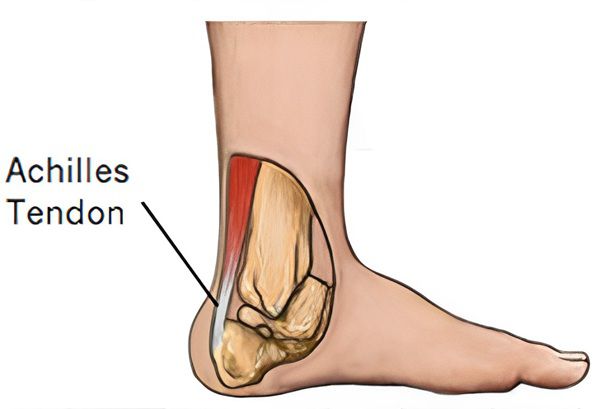

۱۰. آناتومی تاندون آشیل

- تاندون آشیل اتصال مارپیچیشکلی به پاشنه دارد.

- تمرین حرکات چرخشی مچ پا (مثلاً پرونیشین/سوپینیشن، اینورژن/ایورژن – حرکات بردن پا به داخل و بیرون) به بارگذاری فیبرهایی که در جهات مختلف قرار دارند، کمک میکند.

- این ساختار مارپیچ ممکن است در مورد سایر تاندونها نیز صدق کند.